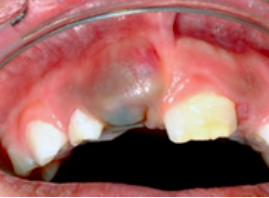

萌牙囊肿

症状表现

常见于儿童萌出的乳牙或恒牙牙冠周围,因组织液或血液积聚所致,是一种生理现象。

牙囊间隙的扩大,有一个鼓包。当与血液混合时,颜色发深。

图片来源:[2]

如何处理

无需治疗。当牙齿通过囊肿萌出后,囊肿会自发消退。如果牙齿在囊肿出现两周内没有萌出,需要带宝宝去口腔科检查。